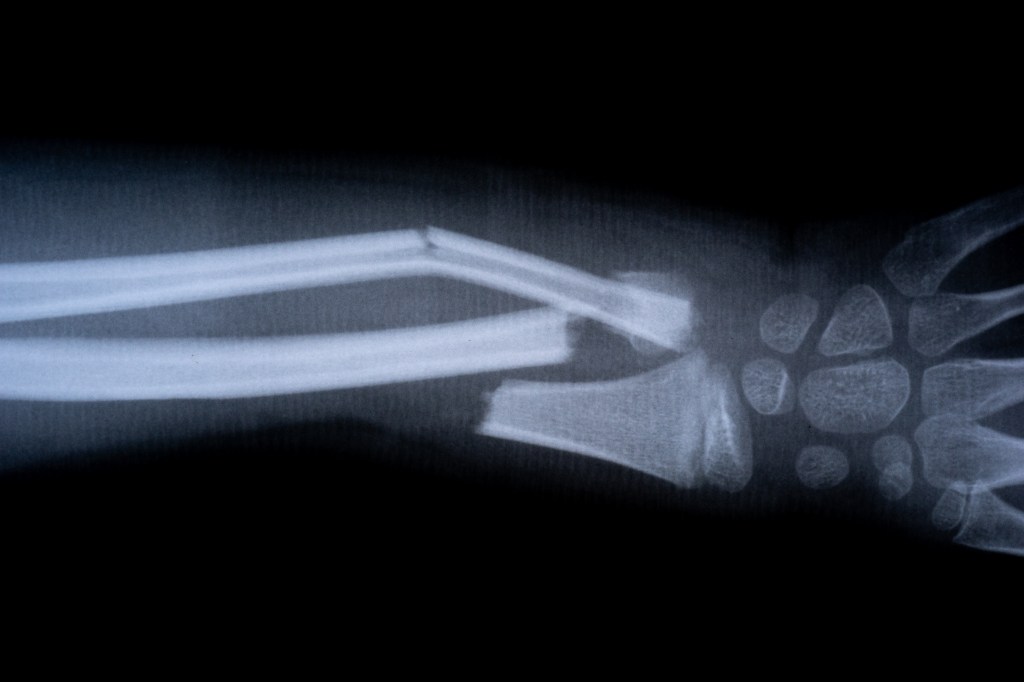

Scientists in China have unveiled a groundbreaking “bone glue” that can heal fractures within minutes, cutting down recovery times that would normally take months.

The product, called Bone-02, was developed by a research team aiming to reduce the need for invasive orthopedic surgeries that often involve metal plates and screws, according to New York Post.

According to Lin Xianfeng, associate chief orthopedic surgeon at Sir Run Run Shaw Hospital in Hangzhou, the adhesive works in blood-rich environments and can fix shattered bone fragments in just three minutes with a single injection.

In one trial, a patient with a wrist fracture was treated through a small incision and healed in minutes — avoiding the need for plates, screws, and follow-up surgeries. Three months later, doctors confirmed the bone had healed fully without complications.

Researchers drew inspiration from oysters, which naturally produce a glue-like substance strong enough to stick to underwater surfaces. Similarly, Bone-02 forms erosion-resistant bonds and has been shown to withstand forces of over 400 pounds.

The glue is also naturally absorbed by the body during healing, meaning patients won’t need an additional procedure to remove implants. Early results suggest it carries fewer risks of infection compared to traditional metal-based treatments.